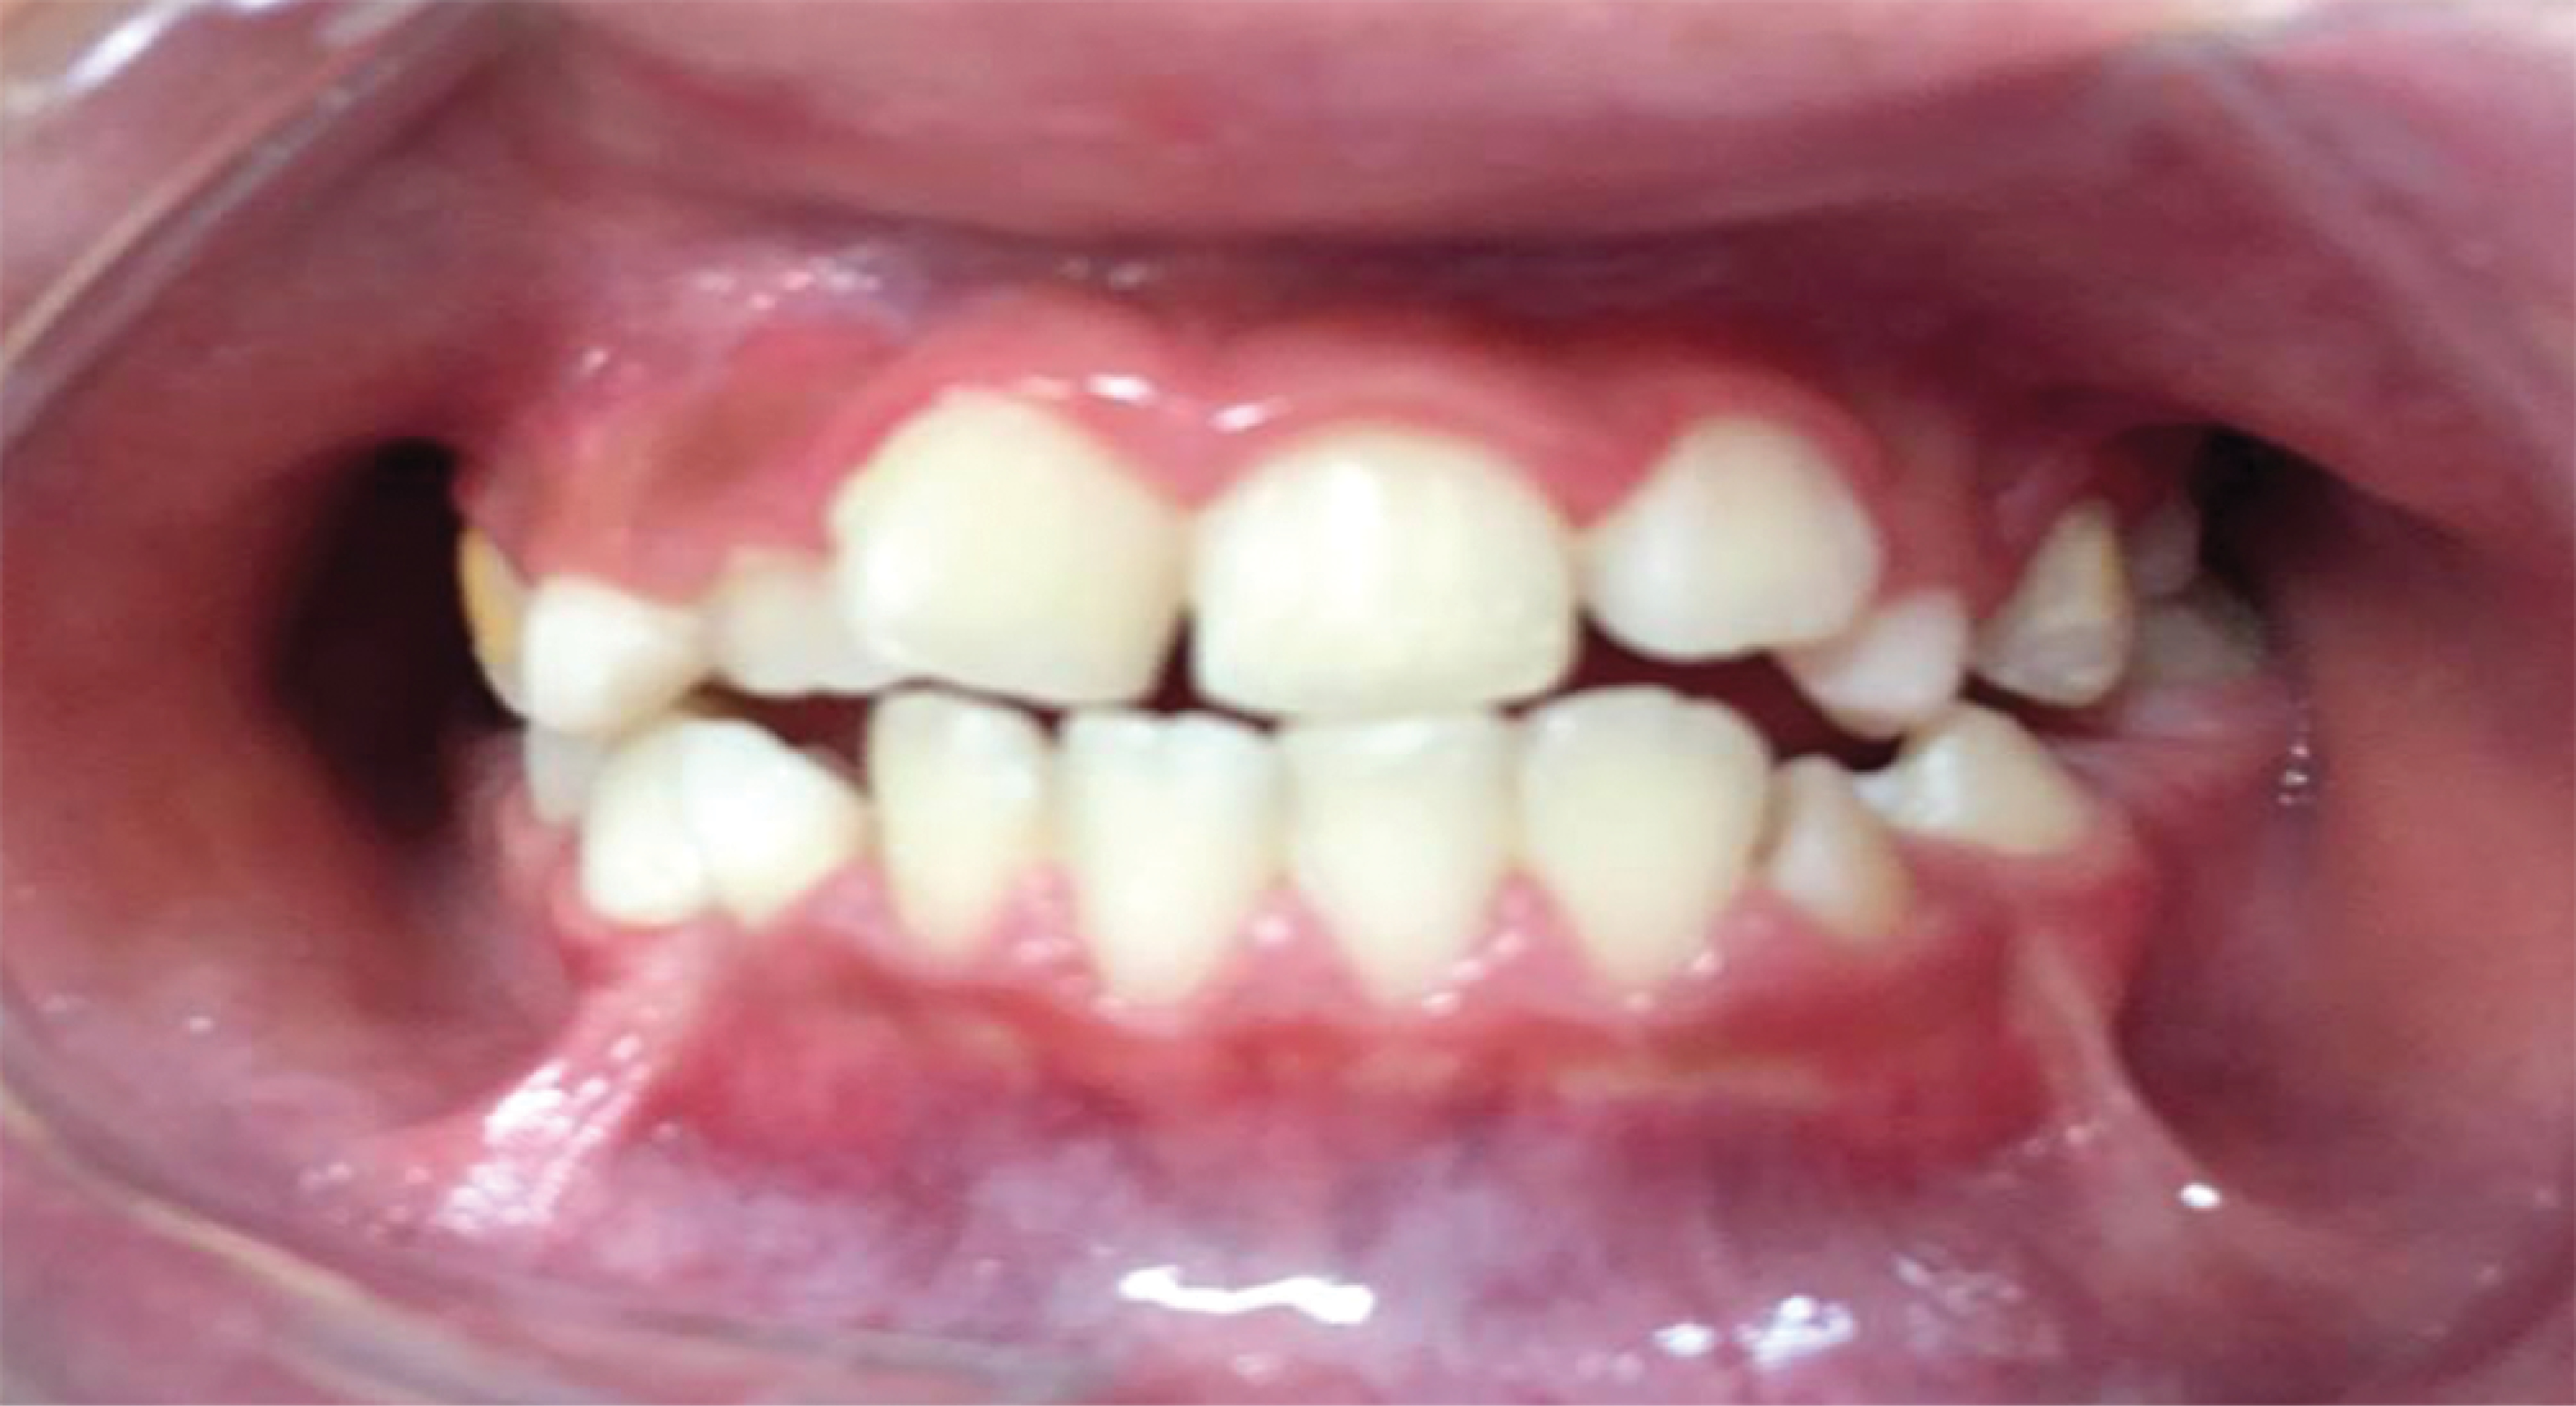

Figure 1